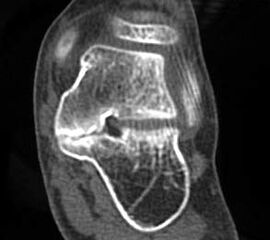

MRT und CT konkurrieren in der Fein-Darstellung der Knochenbrücke, der Beurteilung der nichtbetroffenen Anteile des Subtalargelenkes und der Sekundärveränderungen. Das MRT bietet den Vorzug, bindegewebige und knorpelige Strukturen (Abb. 2) und bei Einsatz von Kontrastmittel auch knöcherne Aktivierungsphänomene genau abzubilden; die knöcherne Feinstruktur und genaue Ausdehnung dagegen ist mit dem Dünnschicht-CT wesentlich exakter darstellbar (Abb.3). In manchen Fällen ist eine 3-D-Rekonstruktion des CT hilfreich. Besonders wichtig ist eine geeignete Schichtebenen-Wahl:

Diagnostisch sollte neben Röntgenübersichtsaufnahmen (indirekte radiologische Zeichen: Dorsaler Traktions-Osteophyt am Taluskopf, „talar beaking“; kontinuierliche Linie der Trochlea-tali-Kontur übergehend in die Sustentaculum-tali-Kontur, „C-Zeichen“ (Abb. 11) 10) immer die dreidimensionale Bildgebung eingesetzt werden. Das MRT (mit Kontrastmittel) kann die Struktur der Brückenbildung und z.B. die Qualität des Restgelenkes (Knorpel-Dicke) besonders gut abbilden; das Dünnschicht-CT zeigt die knöcherne Feinstruktur im Bereich der Coalitio und den oft sehr schrägen Spalt-Verlauf im Frontalschnitt dagegen häufig genauer. Meist findet sich die Überbrückung im Bereich der medialen Facette; die Schichten sollten jedoch bis weit nach dorsal beurteilt werden, da ansonsten dorsomediale Formen übersehen werden können. Rozansky et al 7 unterschieden fünf morphologische Typen auf der Basis von 3-D-CT-Rekonstruktionen. Allerdings ist eine prognostische Zuordnung bisher nicht möglich.